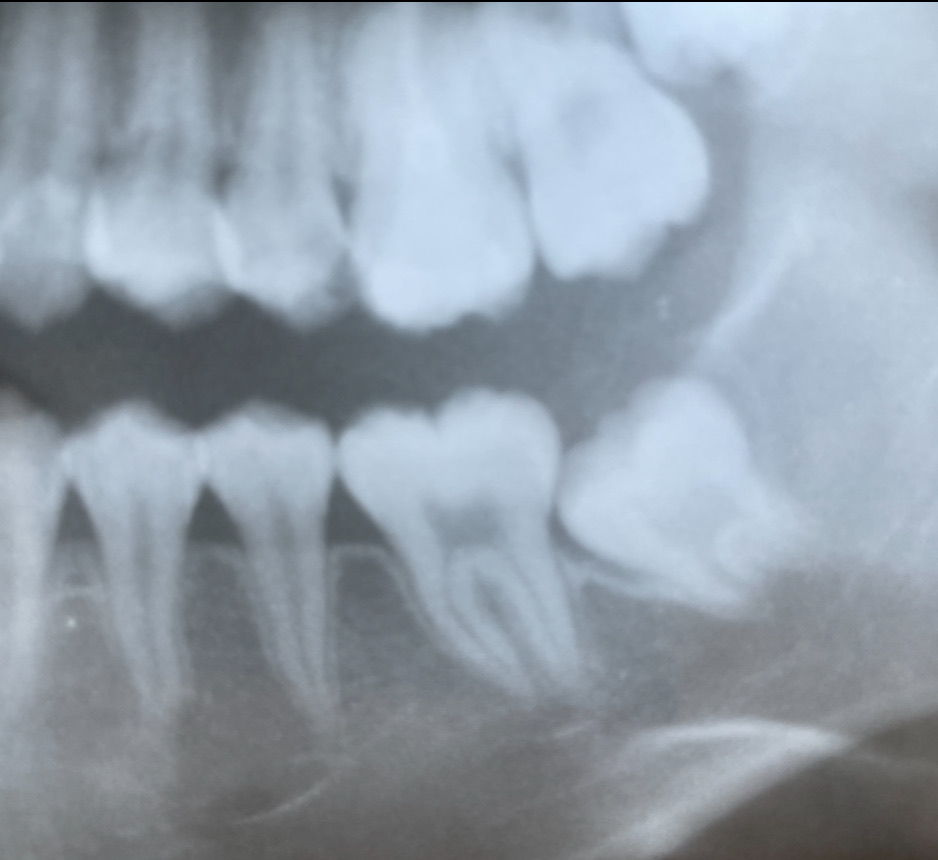

そして、5年後、15才になったときのレントゲン写真がこちらです。

後ろの第二大臼歯が、抜歯してできたスペースを綺麗に埋めてくれました。

ご本人さまにも、快適に日常生活を過ごして頂いています。